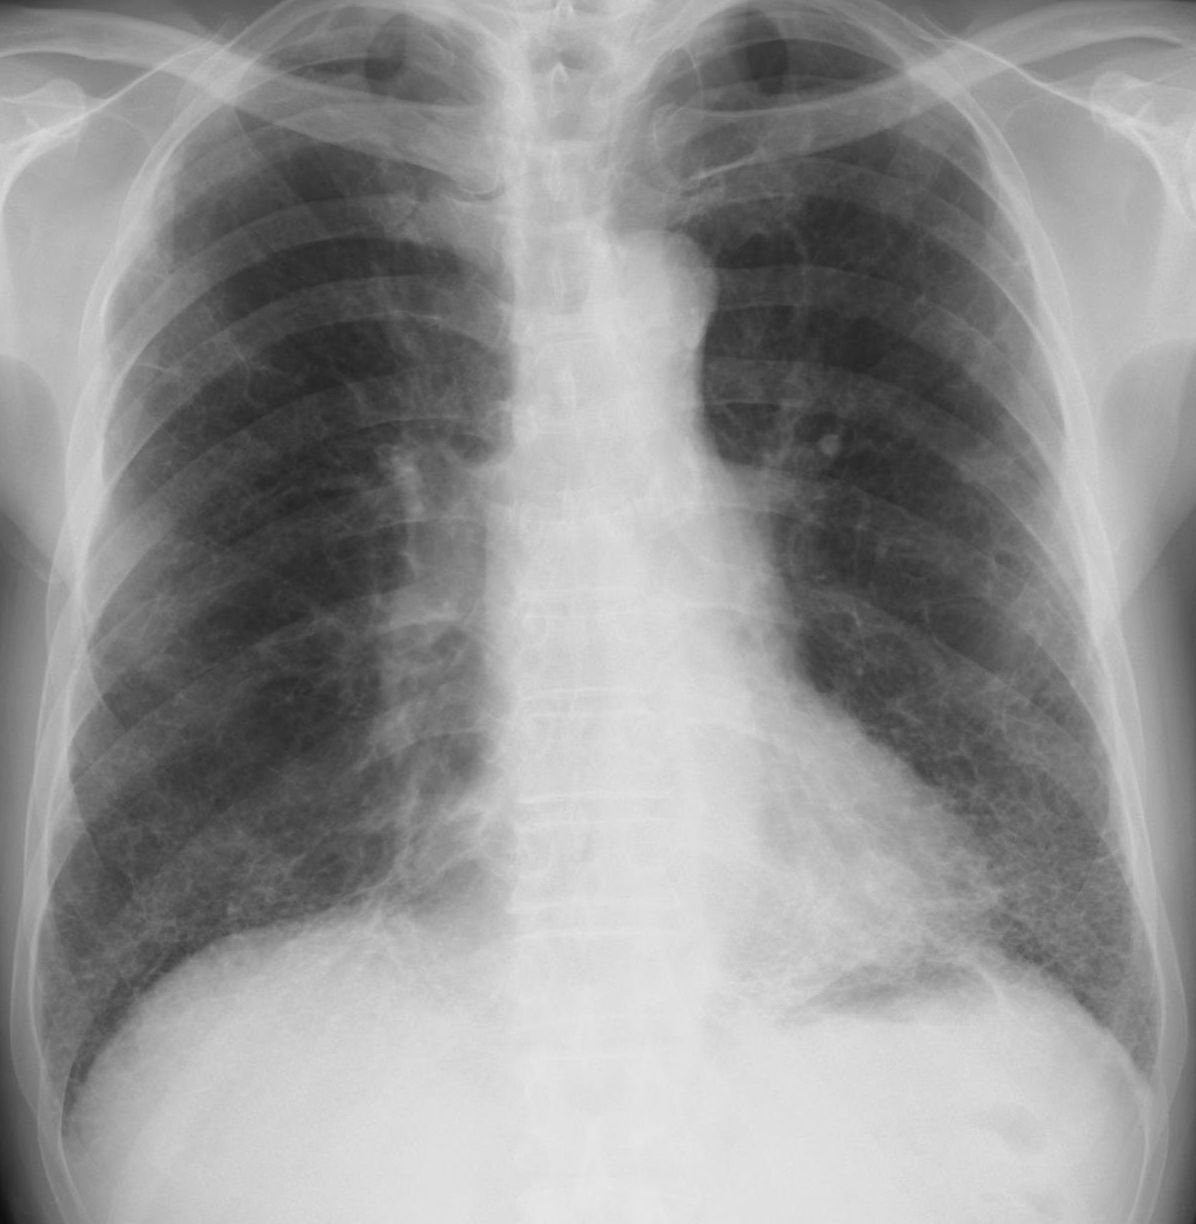

C.肺線維症(間質性肺炎) ①やや線量過多の写真で肺野が幾分黒くなっている。

②肋骨の陰影が薄くとくに肺野ではわかりずらくなっている。

③右心辺縁と左横隔膜の一部がはっきりしない。

④両下肺中心に輪状、線状、網目状陰影が目立ち、蜂巣様。

[評価] 間質の変化中心の間質性肺炎像、肺線維症が考えられる。

肺線維症(軽症例) 肺線維症(やや進行)